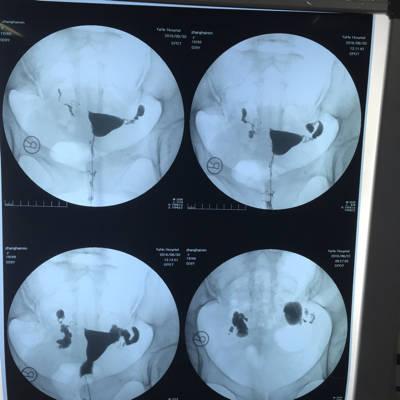

输卵管积水

输卵管积水是指输卵管内口或者内口的积水,它的范围还是存在的,但是输卵管还是有问题的。另外,当输卵管内的积水和卵泡液的形成是,输卵管的纤毛受到过度的拉制,例如爆弹、钳夹,只要没有伤害到输卵管。如果输卵管管腔还是完整的,那就是可以怀孕的,如果积水比较多,那么积水就会出现在沟渠以及阴道处,这也是排卵性的。